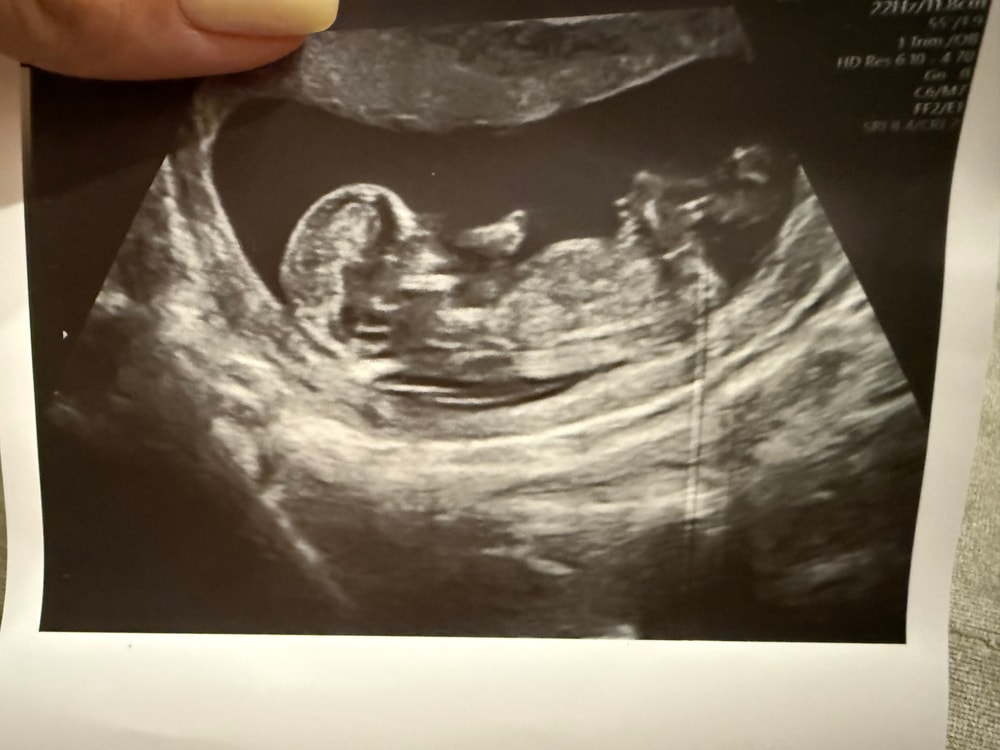

Валерия в Благополучная беременность 4 месяца Пол ребенка Анализы, скрининги Девочки, можно ли как-то по таким снимкам предположить пол ребенка? Посмотрите еще 20 записей на эту тему Отменить Ответить Карамелечка Похоже на мальчика🙂 08.08.2025 Ответить Tatiana А я за девочку ☺️ 07.08.2025 Ответить Анастасия Думаю, что мальчик) Но это скорее гадание) 07.08.2025 Ответить GinBerry Можно, погуглите про половой бугорок. Похоже, что это он у вас на втором фото 07.08.2025 Ответить Преждевременное старение плаценты Локб Скрининг Чаты Беременных Выберите чат: Январята-2026 Февралята-2026 Мартята-2026 Апрелята-2026 Майчата-2026 Июнята-2026 Июлята-2026 Августята-2026